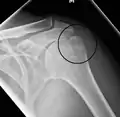

Fracture of the greater tuberosity of the humerus

Multi-fragmented, or comminuted fracture of the proximal humerus with involvement of the greater tuberosity